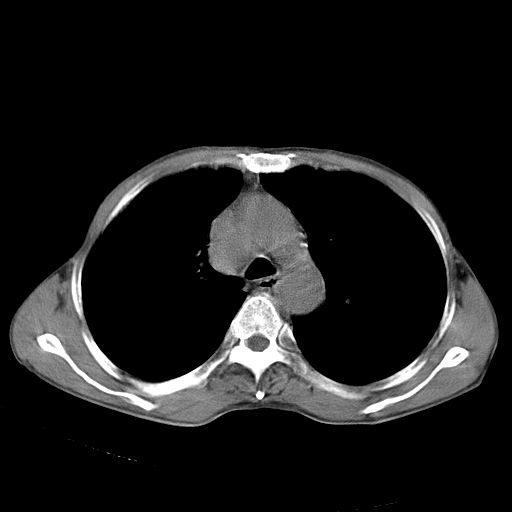

以下是引用苯小孩在2007-5-24 12:47:00的发言:[br]右侧肺门处不均匀密度软组织块影,远端肺组织见斑片模糊影,纵隔内淋巴结明显肿大,边界不清.<纵隔窗第12层面支气管内似见软组织结节>[br]考虑:1、右侧中央性肺癌并阻塞性肺炎并纵隔淋巴结转移可能性大.建议强化或纤支镜进一步检查.[br]2、隆突下淋巴结肿大/食道病变?请做鉴别检查.

以下是引用zhangzhongshou在2007-5-24 12:55:00的发言:[br]1、右肺中叶中心型肺癌并右肺门、隆突下、纵隔淋巴结转移。右肺中叶阻塞性肺炎。

以下是引用jw-830在2007-5-24 15:24:00的发言:[br][br] [br] 考虑右肺中央型肺癌并阻塞性炎症,右肺门及纵隔淋巴结转移。 [br] [br][br]